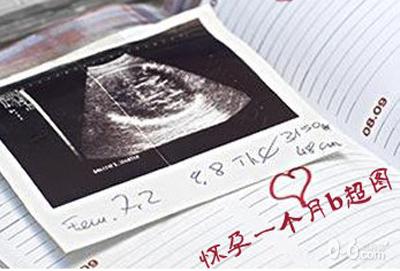

怀孕一个月b超图中可以看出着床后胚胎慢慢长大,受精卵不断地分裂,形成大脑和神经组织的重要时期。一般情况下怀孕前3个月不建议使用b超。

怀孕一个月B超图能看见什么呢?其实在这时间的胚芽,身体分两大部分,非常大的部分为头部,占了身长的一半,头部相连着的躯体,有长长的尾巴,很像小海马的形状。这时人类的胚芽,在外观上,与其他动物的胚芽没有什么区别,手脚因为太小,肉眼还看不清楚。

这个时期的胎儿,眼睛、鼻子、耳朵尚未形成,但嘴和下巴的雏形已经能看到了。血液循环系统器官原型已出现,脑、脊髓神经系统器官原型也已出现;肝脏在这个时期也开始显著发育;心脏的发育较显著,在第2周末成形,从第3周末起开始搏动;与母体相连的胎盘;脐带也从这个时候开始发育了。

胚芽的表面覆盖着绒毛组织,这种组织不久将要形成胎盘。胎儿通过胎盘吸收母体的营养成分,排出代谢产物。